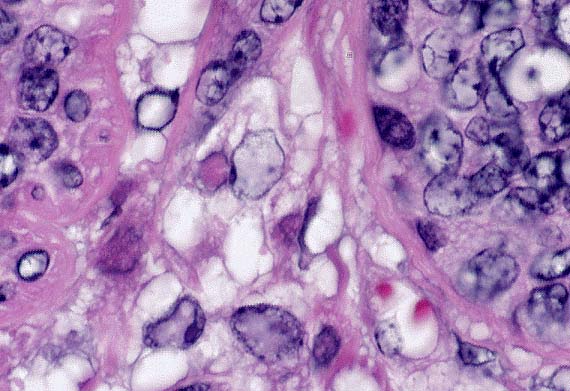

Higher magnification of the field above. (If you look closely, you may be able to imagine a rhabditiform esophagus). (HE, 400X, 51K)

Contributor's Diagnosis and Comments: Chronic, severe multifocal granulomatous nephritis with intralesional rhabditiform nematodes, consistent with Halicephalobus deletrix.

Morphologic Description: There are multifocal to coalescing foci replacing the renal parenchyma. The foci contain cross and longitudinal sections of a nematode with a smooth cuticle, pseudocoelom, a tubular digestive tract lined by low cuboidal epithelium, tapered tail, and rhabditiform esophagus with a corpus:isthmus:bulb ratio of 3:2:1. Mature females, larvae, and eggs are present, and females rarely contain ova in various stages of development. The parasite is surrounded by a mixture of fibrin, neutrophils, cellular debris, epithelioid macrophages and multinucleated giant cells that are contiguous with coalescing infiltrates of plasma cells, lymphocytes, and eosinophils in a loose fibrovascular stroma. Occasional tubules are present among the inflammatory cells, and these are often lined by necrotic or regenerating epithelial cells and contain proteinic and cellular debris.

H. deletrix is distinguished by a uterus that is dorsoflexed at the ovary and ventroflexed at the vulva, a tapered tail, and a rhabditid esophagus with a corpus:isthmus:bulb ratio of 3:2:1. All eight species are considered free-living nematodes found in soil and decaying organic material. However, the free-living stages of H. deletrix have not been identified, and only adult females, larvae, and eggs have been reported from tissues of horses and human beings. The brain is the most commonly involved tissue in horses, followed by the kidneys, oral and nasal cavities, lymph nodes, lungs, liver, ganglia, bone and eye. The parasite may induce an acute syndrome of cerebral vasculitis and hemorrhagic necrosis, as well as granulomatous lesions in brain and other tissues. Renal infections produce cream-colored masses which may resemble neoplasms grossly. The method of infection is unknown. It is presumed that infection occurs by contamination of mucosal, cutaneous, or ocular wounds by larvae in the environment, with hematogenous dissemination accounting for the high incidence of kidney and brain involvement. In addition, pulmonary infection in two foals has lead to the suspicion that infection may occur by inhalation, transplacental, or transmammary routes.